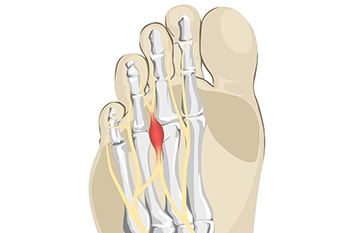

Pain From Morton’s Neuroma

A Morton’s neuroma refers to thickening of nerve tissue at the base of the 3rd or 4th toe. While the precise cause of this condition is unknown, it is thought to form from pressure, irritation, or injury of nerves leading to the toes. This condition can cause one to feel like there is a lump or knot near the ball of the foot, like they are walking on a pebble, or wearing socks that have become bunched up. There can be an achy, sharp, or burning pain in the ball of the foot, or tingling, numbness, or cramping in the forefoot or toes. A Morton’s neuroma can become swollen and painful. One can develop a Morton’s neuroma from wearing shoes that are too narrow where the toes are squeezed together or high-heeled shoes where the body weight is forced onto the ball of the foot. Non-invasive treatments for Morton’s neuroma include wearing properly fitted shoes, with heels less than two inches in height, wide toe boxes, and thick soles, using padding in shoes to take the pressure off the nerve, or taping the feet to redistribute body weight and ease inflammation. Medication and injections can also help relieve pain and pressure of this ailment. Custom orthotics can be made to provide support if one has an abnormal foot structure, such as flat feet or overlapping toes causing the condition. Surgery can be performed if a Morton’s neuroma becomes large or fails to be relieved with more conservative treatment options. Left untreated, a Morton’s neuroma can become worse. For this reason, it is suggested that you visit a podiatrist for a proper diagnosis and treatment that fits the severity of your specific foot problem.

Morton’s neuroma is a very uncomfortable condition to live with. If you think you have Morton’s neuroma, contact one of our podiatrists of Lexington Foot and Ankle Center, PSC. Our doctors will attend to all of your foot care needs and answer any of your related questions.

Morton’s Neuroma

Morton's neuroma is a painful foot condition that commonly affects the areas between the second and third or third and fourth toe, although other areas of the foot are also susceptible. Morton’s neuroma is caused by an inflamed nerve in the foot that is being squeezed and aggravated by surrounding bones.

What Increases the Chances of Having Morton’s Neuroma?

- Ill-fitting high heels or shoes that add pressure to the toe or foot

- Jogging, running or any sport that involves constant impact to the foot

- Flat feet, bunions, and any other foot deformities

Morton’s neuroma is a very treatable condition. Orthotics and shoe inserts can often be used to alleviate the pain on the forefront of the feet. In more severe cases, corticosteroids can also be prescribed. In order to figure out the best treatment for your neuroma, it’s recommended to seek the care of a podiatrist who can diagnose your condition and provide different treatment options.

What is Morton's Neuroma?

Morton’s neuroma, (also referred to as Morton’s metatarsalgia, Morton’s neuralgia, plantar neuroma or intermetatarsal neuroma) is a condition that is caused when the tissue around one of the nerves between your toes begins to thicken. This thickening can result in pain in the ball of the foot. Fortunately, the condition itself is not cancerous.

Morton’s neuroma affects women more often than men with a ratio of 4:1. It tends to target women between the age of 50 and 60, but it can occur in people of all ages. There are some risk factors that may put you at a slightly higher risk of developing the condition. People who often wear narrow or high-heeled shoes are often found to be linked to Morton’s neuroma. Additionally, activities such as running or jogging can put an enormous amount of pressure on the ligament and cause the nerve to thicken.

There usually aren’t any outward symptoms of this condition. A person who has Morton’s neuroma may feel as if they are standing on a pebble in their shoe. They may also feel a tingling or numbness in the toes as well as a burning pain in the ball of their foot that may radiate to their toes.

In order to properly diagnose you, the doctor will press on your foot to feel for a mass or tender spot. He may also do a series of tests such as x-rays, an ultrasound, or an MRI. X-rays are usually done to rule out any other causes for your foot pain such as a stress fracture. Ultrasounds are used to reveal soft tissue abnormalities that may exist, such as neuromas. Your podiatrist may want to use an MRI in order to visualize your soft tissues.

There are three main options for treatment of Morton’s neuroma: Injections, decompression surgery, and removal of the nerve. Injections of steroids into the painful area have been proven to help those with Morton’s neuroma. Decompression surgery has been shown to relieve pressure on the affected nerve by cutting nearby structures such as the ligaments in the foot. Another treatment option would be to surgically remove the growth to provide pain relief.

If you suspect that you have Morton’s neuroma you should make an appointment with your podiatrist right away. You shouldn’t ignore any foot pain that lasts longer than a few days, especially if the pain does not improve.